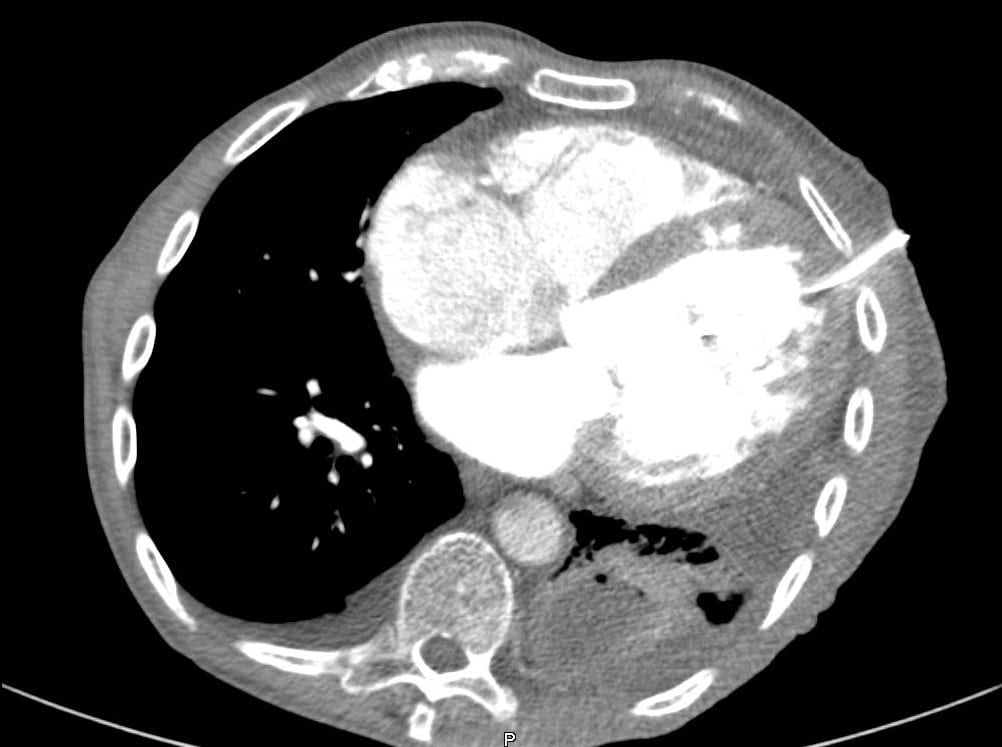

An 86 year-old male presented with shortness of breath.He developed a complication after insertion of a left chest drain. Here is his CT:

The chest drain is in the left ventricle.

This complication was identified at the time by the presence of pulsatile bright red blood coming from the drain.

- Clamping the drain to prevent exsanguination is a good first step!

- Not taking the drain out is a good second step.

- The next step is to prepare the patient for cardiac surgery to remove the drain and repair the heart. In this patient, removing the drain and repairing the heart was achieved via a mini thoracotomy.

In addition to the issues of patient care, this is a sentinel event and appropriate reporting and follow-up needs to be undertaken. The CT below demonstrates how this complication arose…not everything that looks like a left pleural effusion on a plain chest X-ray is one!